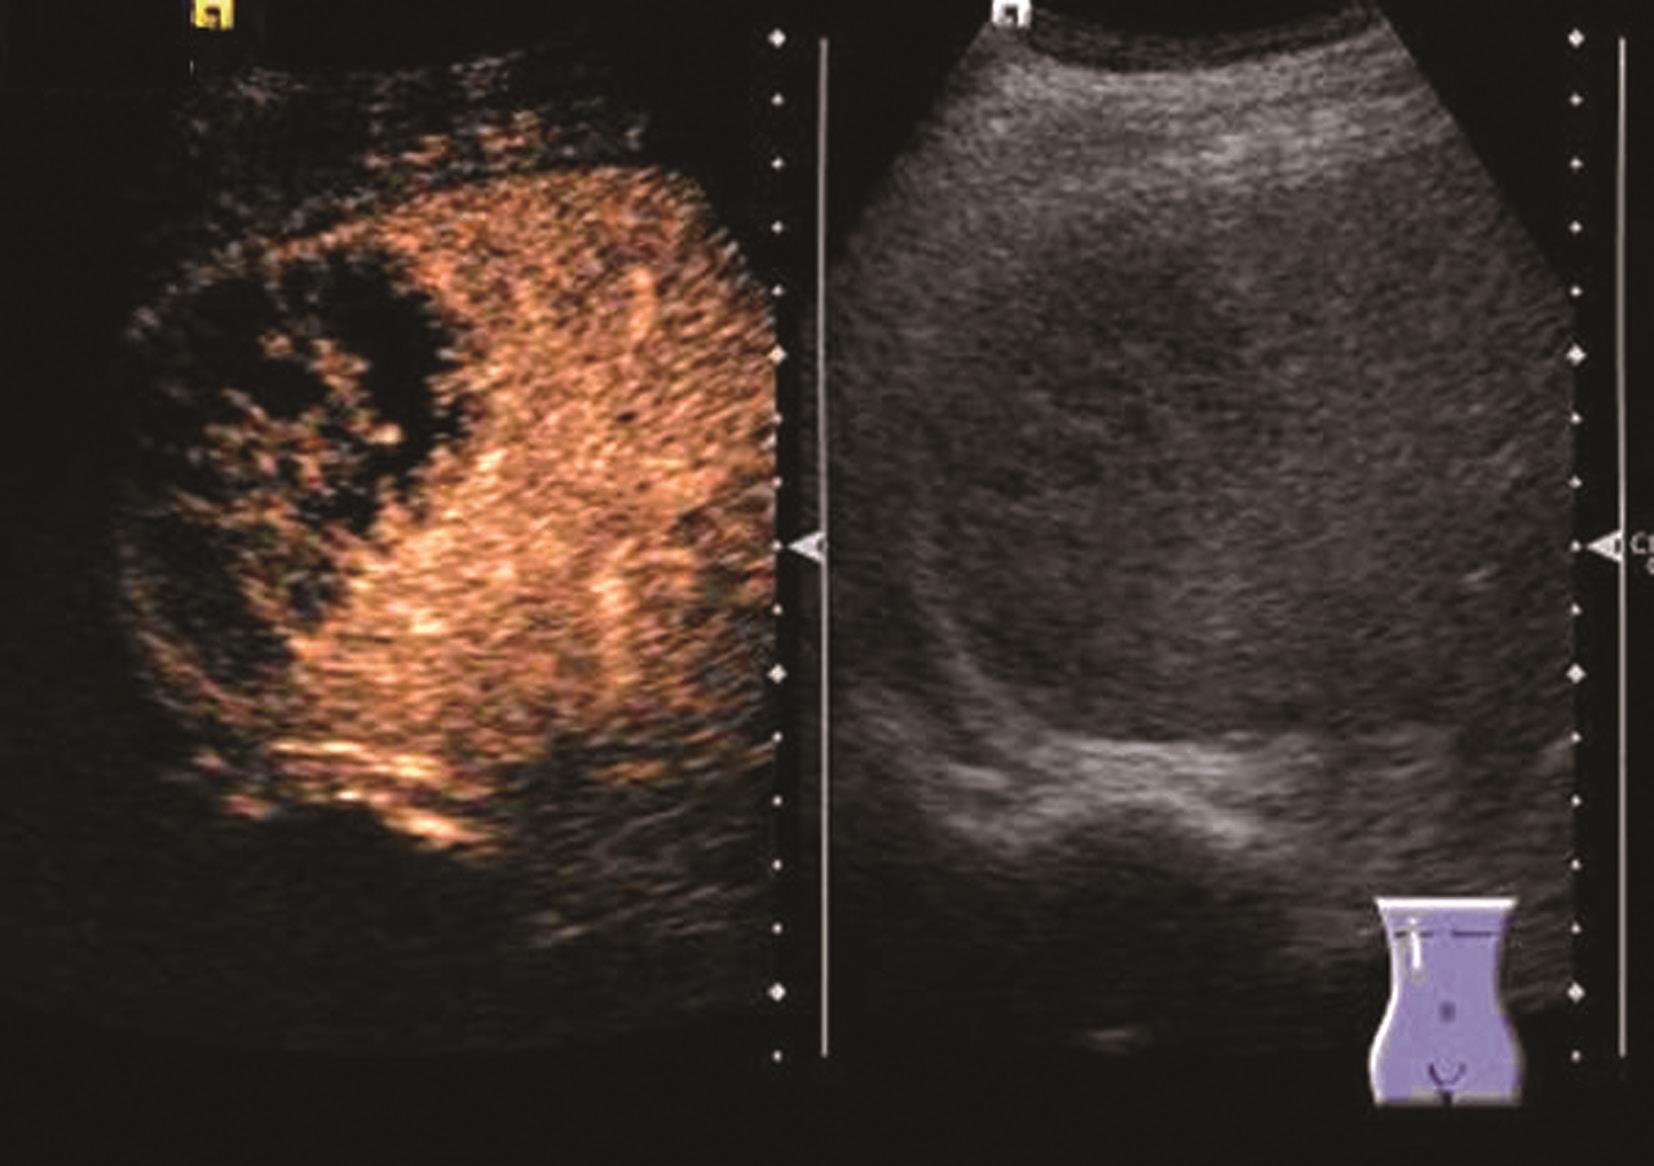

(2)彩色多普勒超声:

尽管血管瘤内血管丰富,但血流速度极为缓慢,彩色多普勒可显示部分血管瘤内部或周边的斑状或短线状血管,频谱均为低速血流。对小血管瘤,尤其位于肝脏深部者则难以检测到血流信号。

(3)超声造影表现:

血管瘤典型的超声造影表现为:动脉相周边结节样或环状高回声增强,门静脉相和延迟相造影剂进行性向心性填充,填充可以是完全性的或部分性,60%~80%的肝血管瘤表现为这一典型特征。造影剂填充的速度根据血管瘤的大小而不同,小血管瘤只需1min,大的可能需要10min。20%~30%肝血管瘤内含有丰富的动静脉短路,充填时间会减短到1min甚至几秒,因此造影后的60秒内观察肝血管瘤的增强特征是非常重要的。如果瘤内有纤维化或栓塞,造影剂填充不完全,这种情况也可能发生在较小的血管瘤。如果有典型的造影增强行为可以诊断血管瘤,而不需进一步其他影像检查。肝血管瘤超声造影动脉期、静脉期及延迟期超声声像图表现如图5-21-13~图5-21-15所示。